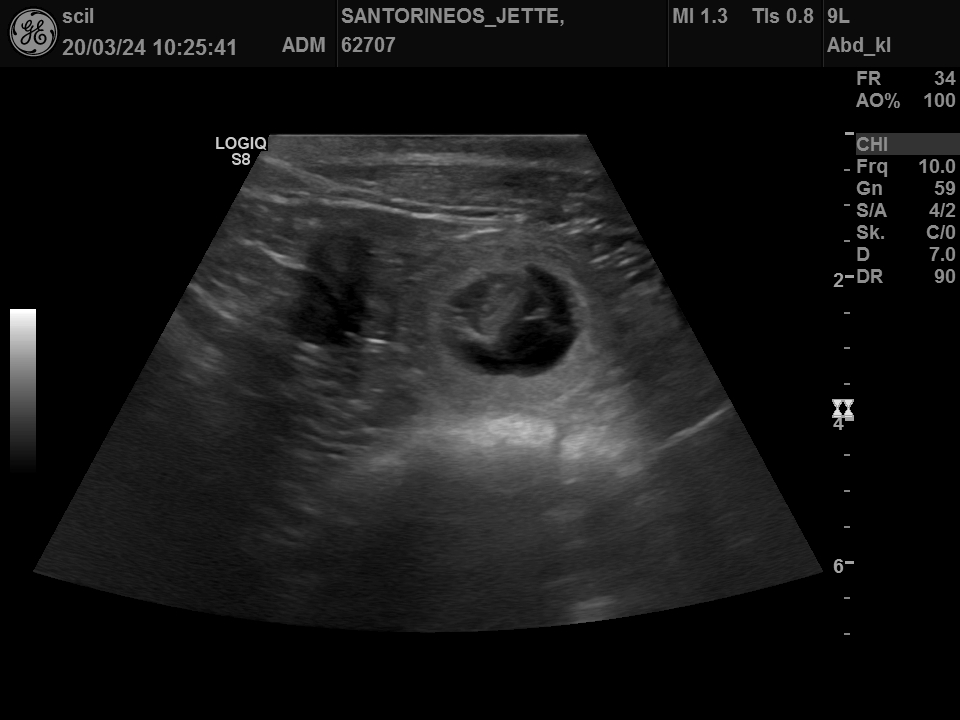

20.03.2024 Jette ist lt. Ultraschall tragend |